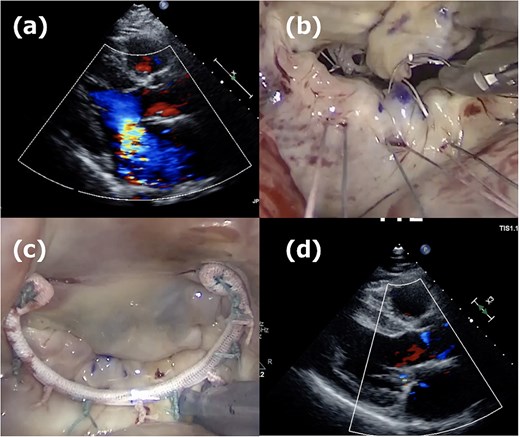

A 52-year-old man presented with chest discomfort on exertion. Transthoracic echocardiography (TTE) revealed severe MR due to a large prolapse of the A2 segment (Fig. 1a). Minimally invasive mitral valve repair was performed through right-sided small thoracotomy. The prolapsed A2 segment was treated with four 22-mm-ePTFE loops (CV4, Gore-Tex, W.L. Gore & Associates, Flagstaff, AZ) attached to the anterior papillary muscle. These loops were fixed to the A2 segment with 5/0 polypropylene sutures (Prolene, Ethicon, NJ) as shown in Fig. 1b. For annuloplasty, a 36-mm CG-Future band (Medtronic, MN) was applied (Fig. 1c). Intraoperative transesophageal echocardiography (TEE) and postoperative TTE showed no residual MR (Fig. 1d), and the patient was discharged on postoperative day 8. At a routine outpatient follow-up clinic 3 weeks later, a severe systolic murmur was detected, and TEE revealed a moderate MR. Partial prolapse of the A2 segment, which was treated at the first operation using the loop technique, was observed (Fig. 2a), and the lactate dehydrogenase level was 1599 U/L, indicating hemolysis. Although the patient remained asymptomatic, reoperation was recommended due to his relatively young age.

First operation images. (a) Severe mitral regurgitation caused by A2 prolapse. (b) Intraoperative image showing the placement of four 22-mm ePTFE loops fixed to the A2 segment with 5/0 polypropylene sutures. (c) The 36-mm CG-future band (Medtronics) was applied for mitral annuloplasty. (d) One week postoperative echocardiogram showing no residual mitral regurgitation.